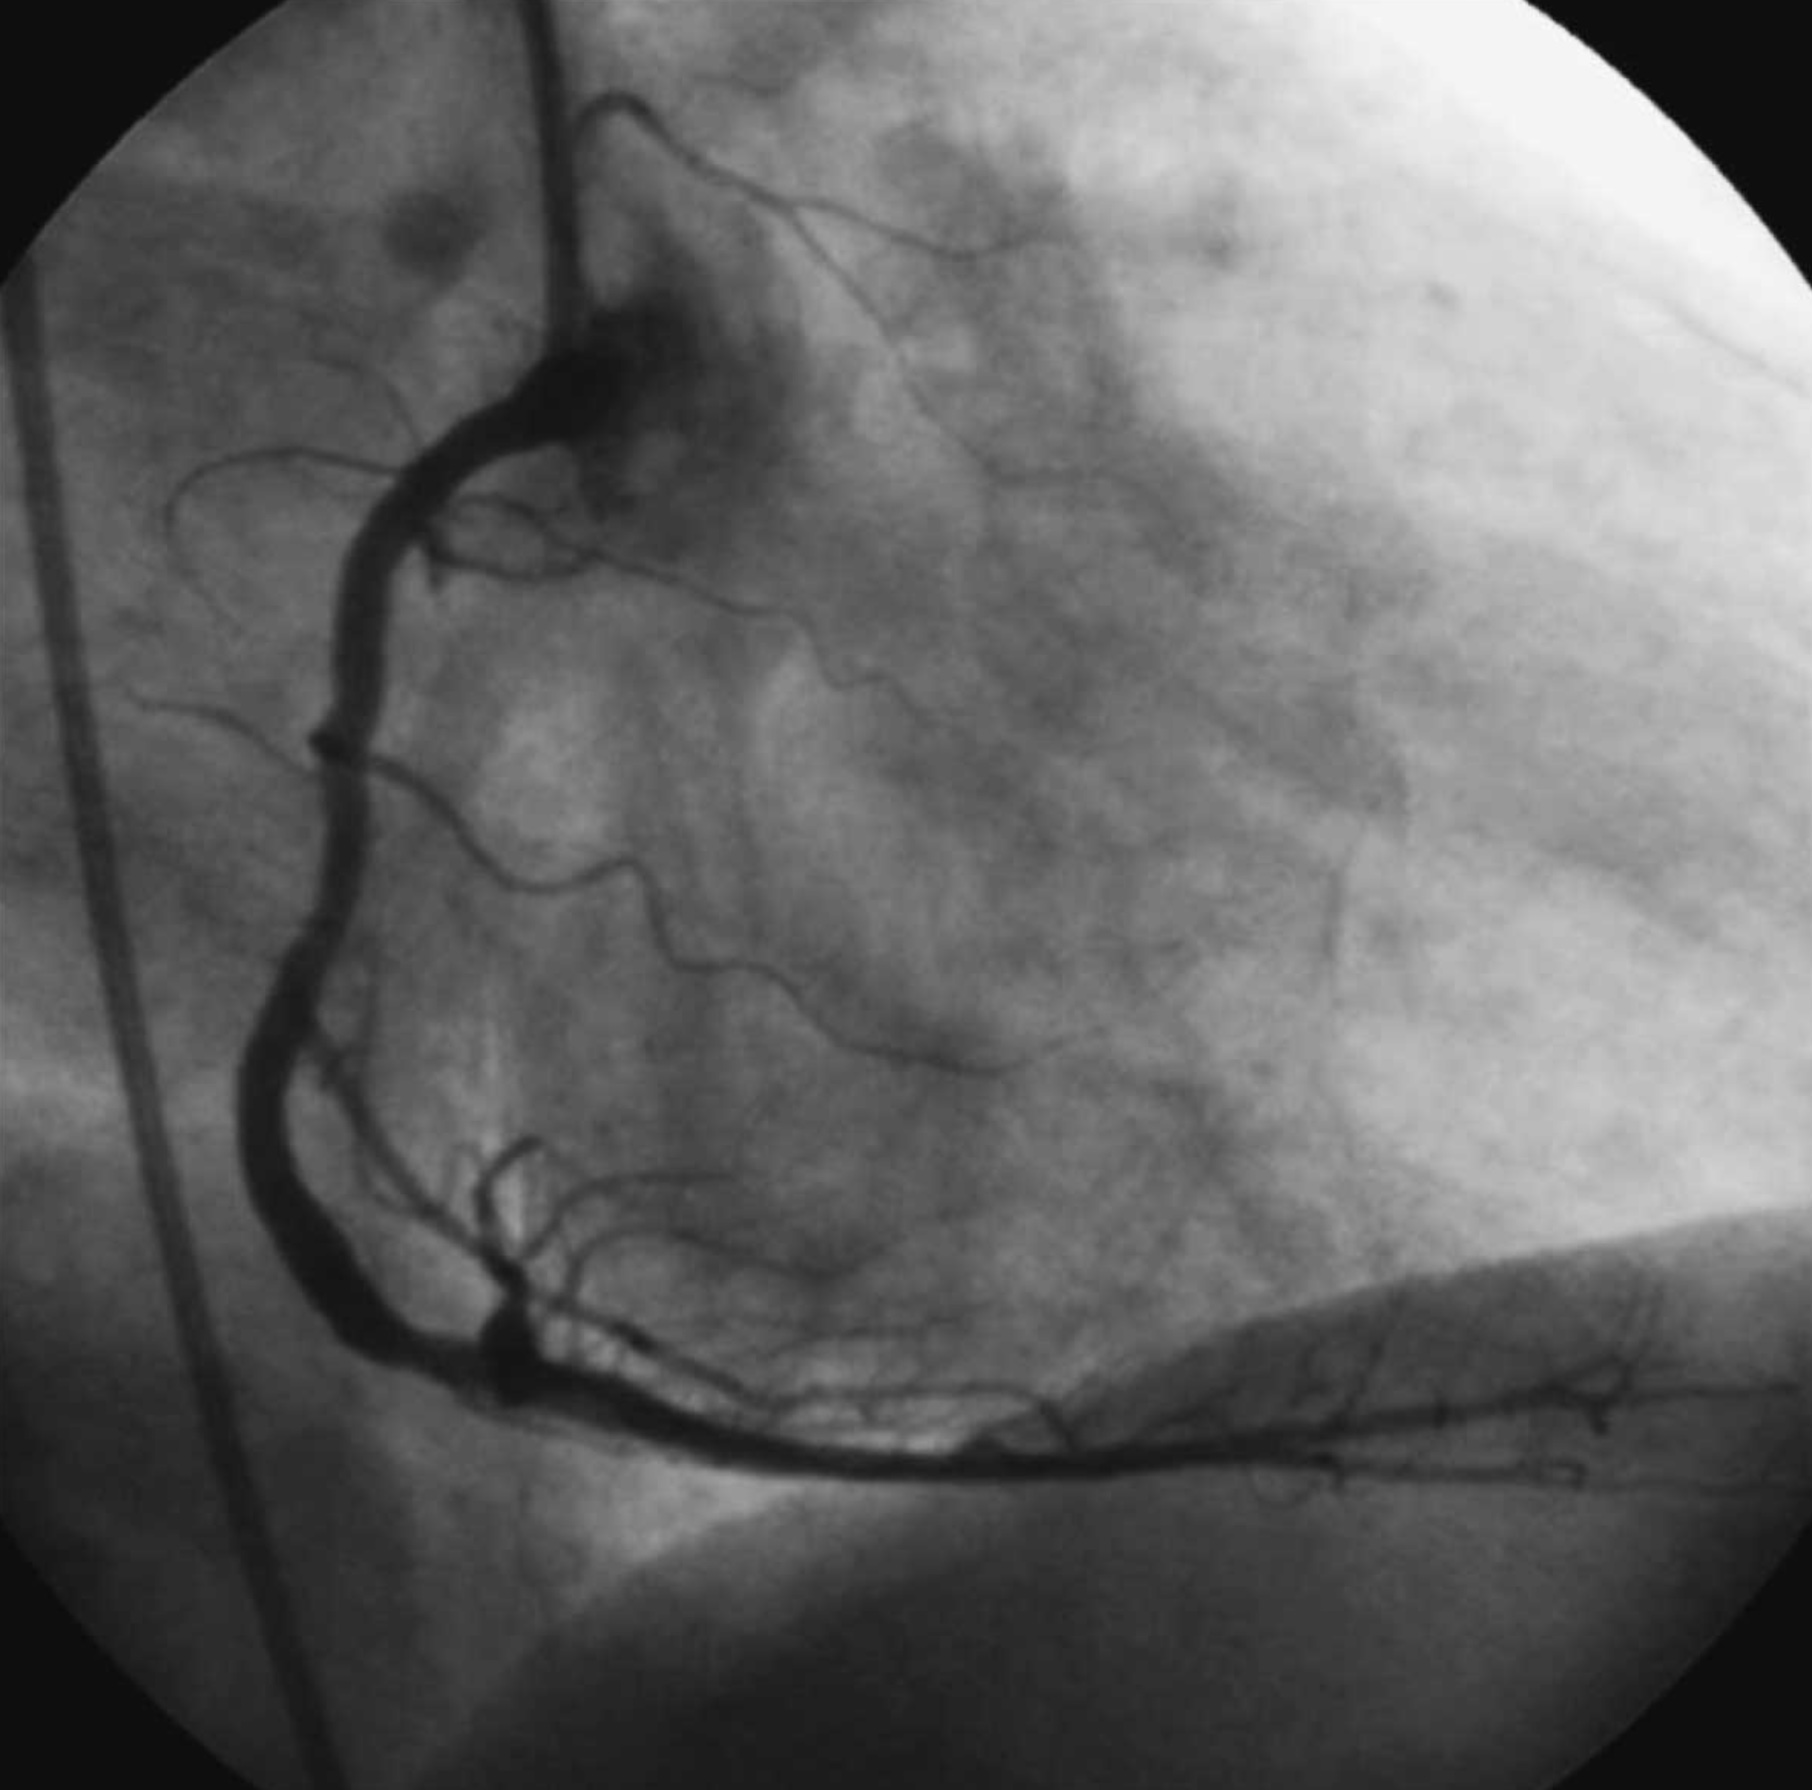

1. An 63 year old man has a heart arrhythmia. Upon further investigation, an angiogram shows an occlusion of the proximal right coronary artery. Why would this potentially cause arrhythmia? Discuss the anatomy and relationships of the right coronary artery and branches as well as the complementary venous drainage. Include mention of any commonly seen anatomical variances, if any.

2. A patient is shown to have a partial occlusion of their anterior interventricular artery (left anterior descending artery). Discuss the anatomy and relationships of the left coronary artery and branches as well as the complementary venous drainage. Why is an occlusion in this artery especially dangerous and what potential surgical solutions can be used as treatment? Include mention of commonly seen anatomical variances, if any.